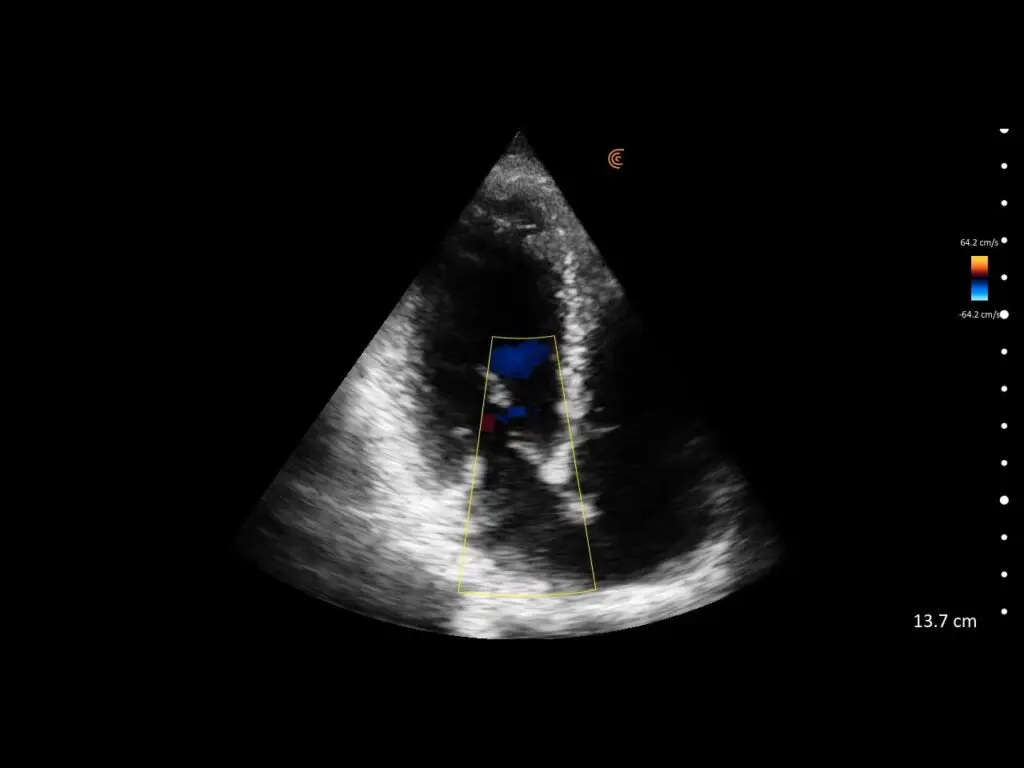

T-Mode es un enfoque innovador para la educación en ecografía diseñado para mejorar sus habilidades de escaneo utilizando la potencia de la inteligencia artificial en aplicaciones de Estética y Cirugía Plástica. Cette technologie novatrice superpose des couleurs distinctes, des motifs et des étiquettes pour identifier et différencier les structures anatomiques et les couches de tissu.